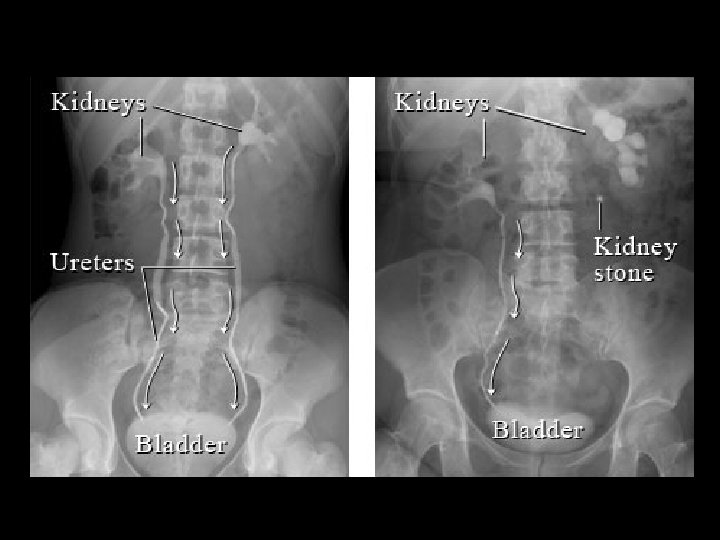

Močovod (Ureter) • 25 -30 cm, průsvit 4 -7 mm • 3 části: pars abdominalis, pelvica, intramuralis • 3 zúžení – nebezpečí zaklínění kamene → obstrukce → hydronefróza → nefukčnost ledviny – při výstupu z pánvičky – při křížení vasa iliaca communia vlevo / externa vpravo – při vstupu do močového měchýře (pars intramuralis) • sliznice složena v řasy → hvězdicový průsvit – lamina propria obsahuje řídké vazivo • Waldeyerova ureterová pochva • retroperitoneální orgán – adventicie obsahuje tukovou tkáň • peristaltický transport moči do měchýře • kříží řadu útvarů

Nemoci močových cest • • nefrolitiáza hydronefróza ruptura pánvičky vezikoureterální reflux uroinfekce urolitiáza + renální kolika divertikly nádory (papilomy, papilokarcinomy)

Léčebné zásahy • LERV (litotripse extrakorporální rázovou vlnou) = ESWL (extracorporeal shock wave lithotripsy) • URS (ureteroskopická lithotripse) • sondáž močovodu (endoskopické zavedení stentu)